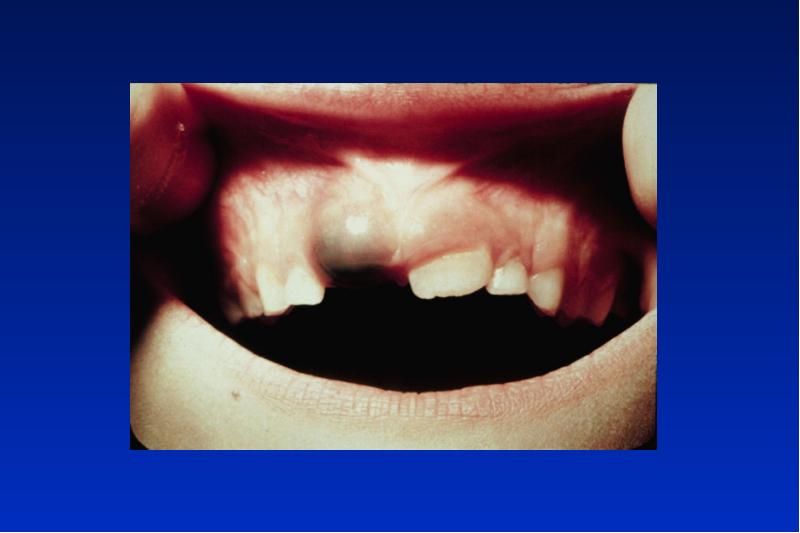

- 23. Gorlin-Goltz Syndrom autosomal dominanter Erbgang Symptome: multiple